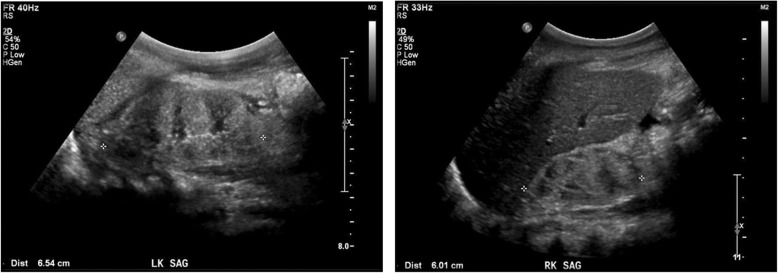

A 5-year-old nonconsanguineous girl of African American and Hispanic origin presented with nephrotic syndrome, including nephrotic-range proteinuria (UPC of > 29 mg/mg), edema, and hypoalbuminemia. Her initial serum creatinine was 654 μmol/L. Other pertinent laboratory evaluation at time of presentation included albumin of 19 g/L, BUN of 38 mmol/L, potassium of 6 mmol/L, bicarbonate of 12 mmol/L, calcium of 1.7 mmol/L, phosphorus of 2.5 mmol/L, and parathyroid hormone of 396 ng/L. She was oligoanuric and hemodialysis was initiated. An ultrasound of her kidneys showed diffuse echogenicity and loss of corticomedullary differentiation (Fig. 1). Her history was significant for developmental delay and short stature. Her proteinuria presented in the setting of a previous respiratory illness but was not investigated. She has a normal-looking face and without dysmorphic features which was confirmed by the hospital’s geneticist. An ophthalmological examination did not show cataract or retinal changes. She has normal looking ears and exhibited normal hearing. She was normocephalic and did not have an exam consistent with GAMOS and no uro-genital anomalies were identified. She had normal birth history, and her family history was not significant for renal, cardiac or neurological development problems.

Fig. 1.

Renal ultrasound at presentation. The patient’s kidneys were notable for small size, diffuse echogenicity and loss of corticomedullary differentiation. Average kidney size for 5-year-old children is 8 cm, however she was small for age, and for a 90 cm tall child the average kidney size is 7.1 cm with 95% prediction limits of 5.8 to 8.3 cm. The ultrasound was performed at the time she was anuric, hence the renal pelvis appears to be collapsed